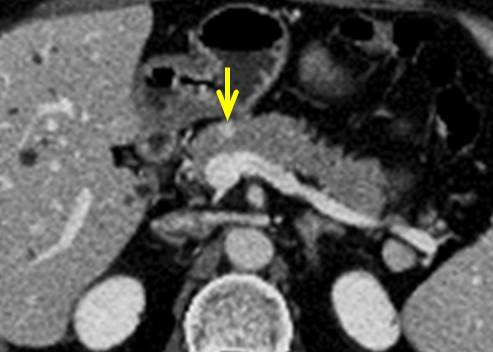

CT:

主膵管の狭窄部位(黄色矢印)は認識できますが、腫瘍は全く認識できません。

MRCP:

主膵管の狭窄(黄色矢印)と尾側主膵管の拡張を認めます。

超音波内視鏡(EUS):

大きさ10mmの低エコー腫瘍(黄色矢印)をはっきりと認識できます。

超音波内視鏡下穿刺吸引法(EUS-FNA)で膵癌と診断できました。

【病理診断】大きさ15mmの浸潤性膵管癌でした。

膵頭十二指腸切除を施行し完全に切除ができました。pT1cN0M0 pStageIAでした。